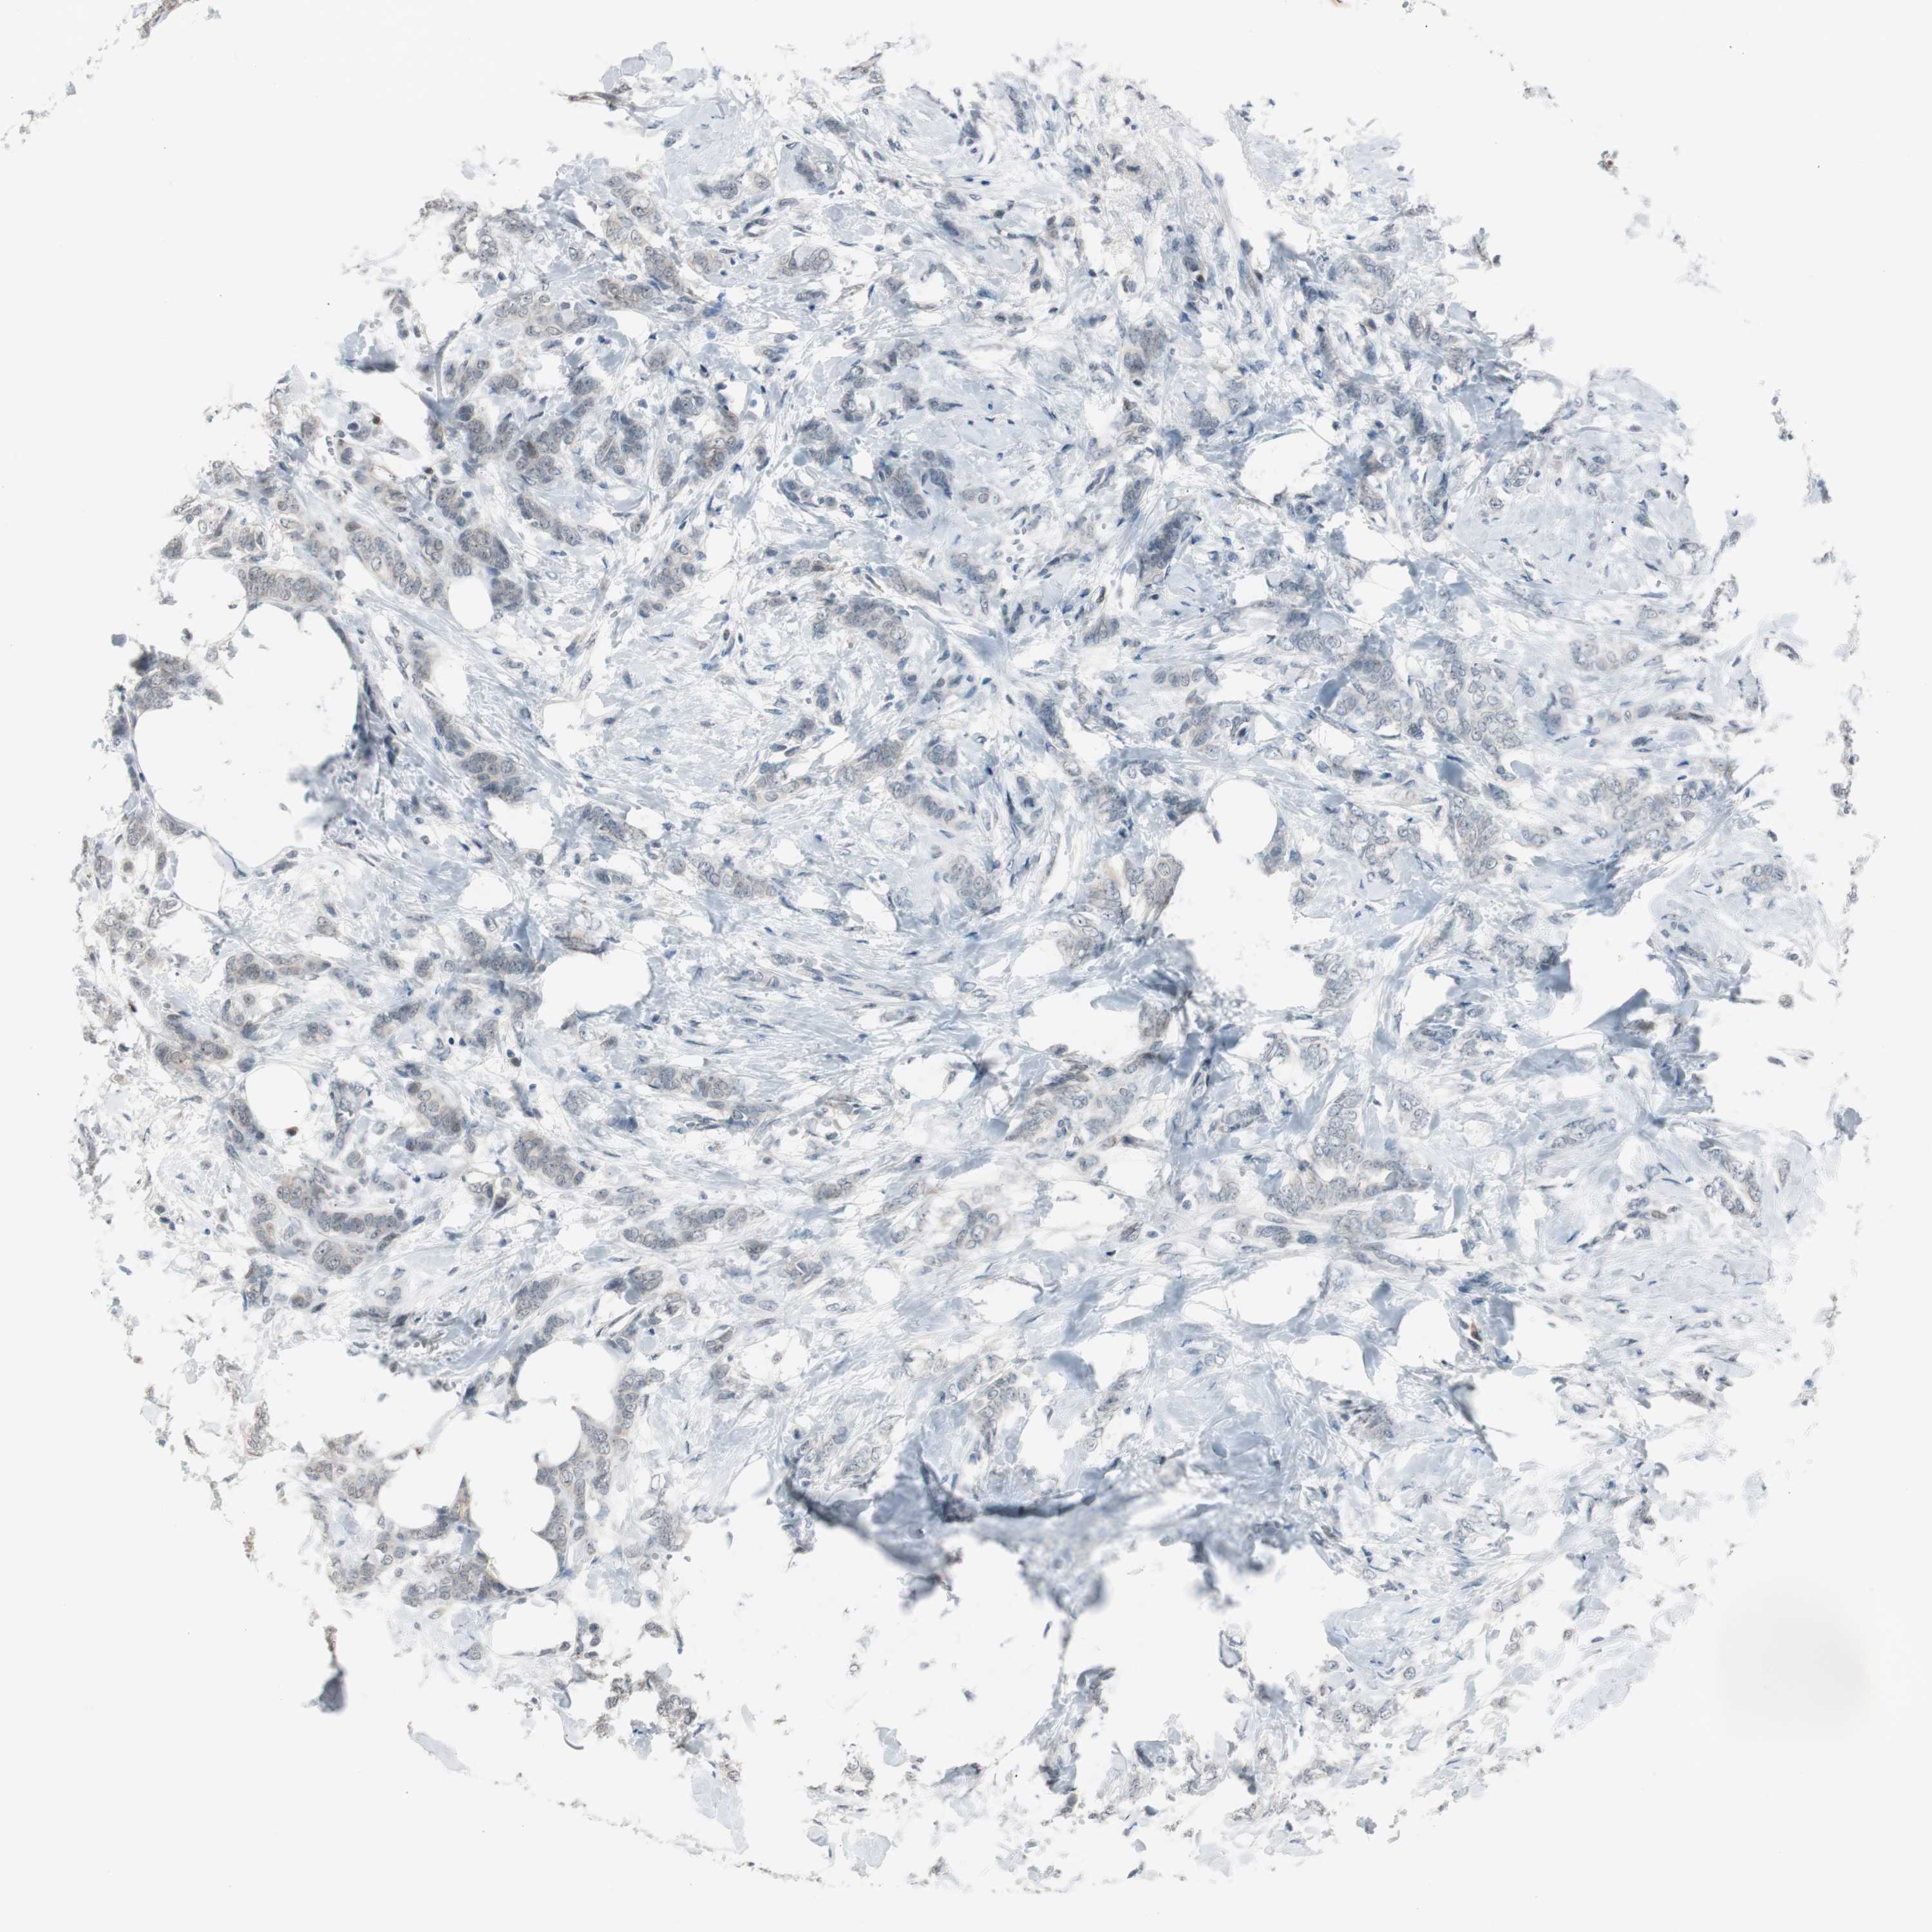

BRCA TCGA BRCA VALIDATION PROTEIN EXPRESSION

ANTIBODIES

AND

VALIDATION